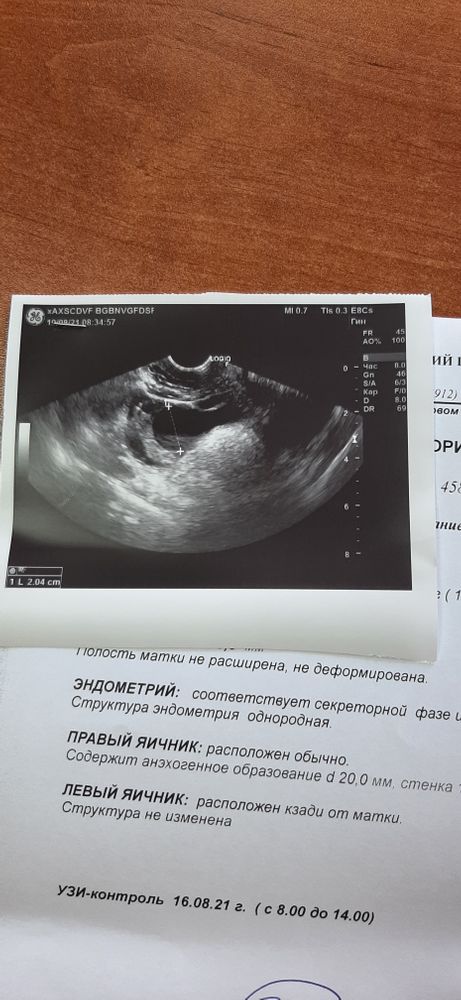

Судя по описанию жт отсутствует (оно всегда с кровотоком), эндик во второй фазе должен быть трехслойный (вот тут не уверена, не буду врать), но жт точно с кровотоком должно быть, а у Вас по видимому фоликулярная киста и О не было

Вам точно врач сказала киста ж.т.,? Просто она тут же указывает что без кровотока, я думала если киста жтела то кровоток должен быть, а вот у фоликулярной нет его

На фолликулярную кисту похоже больше. Если это так, значит он не лопнул - овуляции не было.

Похоже больше на фолликулярную кисту.